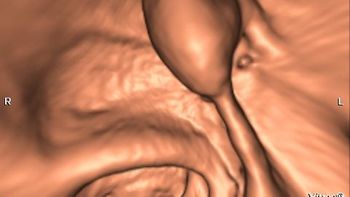

Compared with stool-based non-invasive screenings, CT colonography performs best for colorectal cancer screening and detection.

Implementing a radiomics-based machine learning algorithm allows CT colonography to differentiate between benign and pre-cancerous polyps with high sensitivity and specificity.